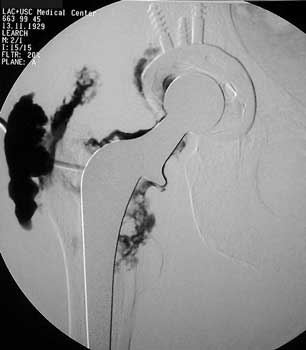

Arthrographic evidence of looseningcontrast enters

abnormally widened interface Gruen zone 1 and 2

Arthrographic evidence of cup looseningcontrast enters

abnormally widened interface Gruen zone II and III

Aspiration of hip after removal of prosthesis. Needle placed

at femoral edge where fluid collects. Needle should not be placed in acetabular

area, which may not be fully intact, risking needle entry into pelvic cavity.